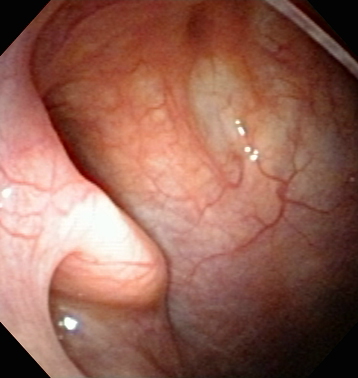

3.眼で見るのどの病気の紹介。